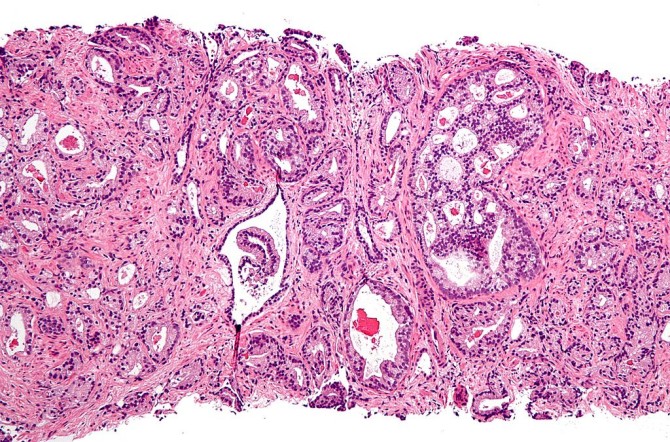

Tejido de cáncer de próstata con una puntuación de Gleason 4. (Foto: Wikimedia Commons)

El cáncer de próstata es un tipo de cáncer que sucede frecuentemente, pero no siempre es agresivo: mueren más hombres con cáncer de próstata que del propio cáncer de próstata. Sin embargo, su tratamiento tiene muchas consecuencias para la calidad de vida de los pacientes, así que hacer un pronóstico de su agresividad es un paso importante a la hora de elegir un tratamiento. Para determinar esta agresividad se toman de la próstata trocitos de tejido (biopsia) que después son examinados por un patólogo. La “puntuación de Gleason” se emplea para clasificar las biopsias en cinco grupos, que indican el riesgo de morir de cáncer de próstata. Sin embargo, estamos ante un proceso subjetivo; si el paciente llegará a ser tratado y cómo, dependerá del patólogo que examina y valora el tejido.

Pronósticos de agresividad más precisos